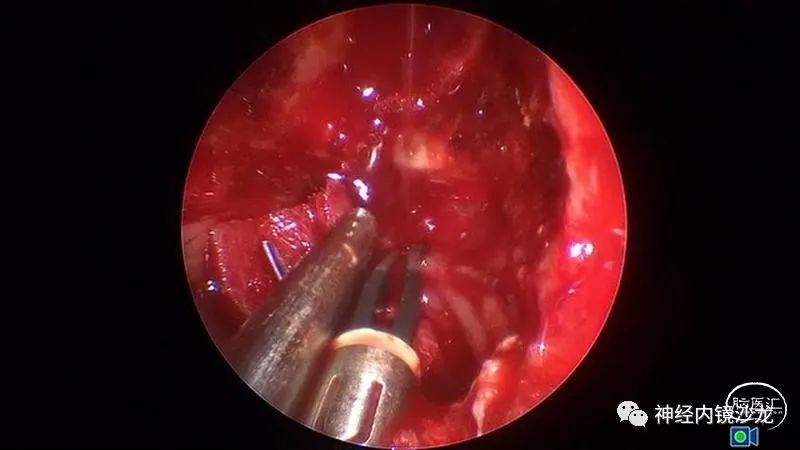

手术暴露充分术野,从蝶骨平台到斜坡,从眼眶到眼眶。切除大块钙化部分肿瘤后,我们找到肿瘤包膜和下丘脑、视觉通路之间的清晰的分离平面。切除结束时,发生了后交通动脉从大脑后动脉撕脱导致的动脉出血。采用单轴持夹器放置一个成角的动脉瘤夹,以夹闭损伤部位并保证供血动脉不狭窄。术后即刻和晚期磁共振成像和CTA检查显示肿瘤全切、无卒中、无假性动脉瘤形成。

术后第9天,患者出现因为鼻中隔皮瓣坏死导致的神经功能减退和脑内积气。尝试了两次用鼻腔侧壁粘膜瓣进行鼻内修复均未成功。然后采用颞顶筋膜瓣并将其从颞部转移至翼颚窝,并成功修复颅底缺损。患而恢复良好,无神经功能异常。